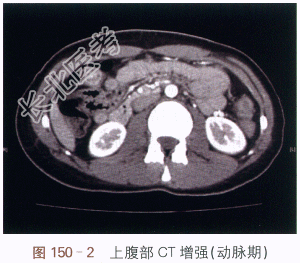

CT平扫(见图150-1)结肠肝区内可见软组织密度影,但无法与肠内容物分辨,很容易漏诊;增强CT(见图150-2)可见结肠肝区内侧管壁不规则增厚,动脉期可见多发迂曲血管显影,周围增厚的管壁轻度强化;选择性肠系膜上动脉造影(见图150-3)提示可见结肠肝区异常血管团、迂曲供血动脉及增粗的引流静脉,实质期可见圆形异常染色;内镜检查证实为肠壁息肉,表面可见出血(见图150-4)。